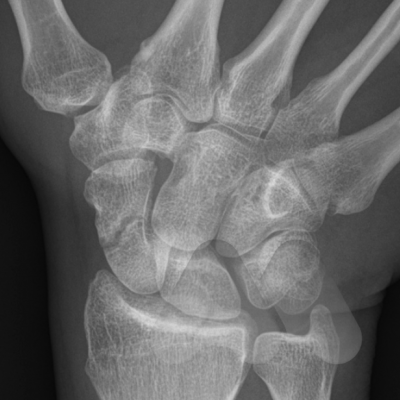

The Scaphoid is one of the eight carpal bones that make up the wrist. It is the commonest carpal bone to be fractured and is more common in young men. The injury occurs often from a fall onto an outstretched hand, sports related injury or a sudden torque injury from power tools. Scaphoid fractures tend to cause swelling and pain on the radial (thumb) side of the wrist and can often be overlooked as a wrist sprain. Despite seeking medical attention, there is a high rate of missed diagnoses due to many fractures not easily seen on initial X-Ray. The scaphoid has an unusual blood supply which can affect it’s healing. It is the key bone that stabilises the wrist and if a fracture is missed or does not heal, this can lead to collapse and arthritis in the wrist at an early age. If you have pain on the radial side of the wrist following an injury that continues for longer than a week, you should seek medical attention.

If initial X-Rays do not show the fracture but there is persistent pain and swelling in the radial side of the wrist, your doctor may ask you to have a CT or MRI scan to give more detailed imaging of the area. This can identify occult scaphoid fractures and the amount of displacement or other injured structures in the area such as distal radius fractures, scapholunate ligament injuries, trapezium fractures or other ligamentous injuries. This helps guide you and your doctor’s choice of treatment.